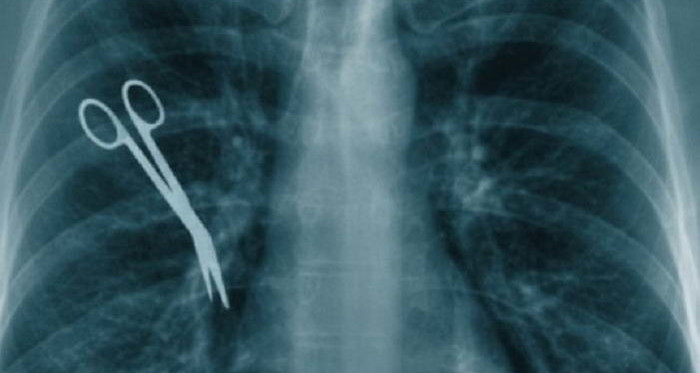

طبيب ينسى مقص في بطن المريضة بعد عملية جراحية بمصحة خاصة بالعاصمة

قررت مريضة مقاضاة طبيب جراح و مصحة بالمركز العمراني الشمالي بالعاصمة بعد أن تبين أن الطبيب نسي مقصّا...